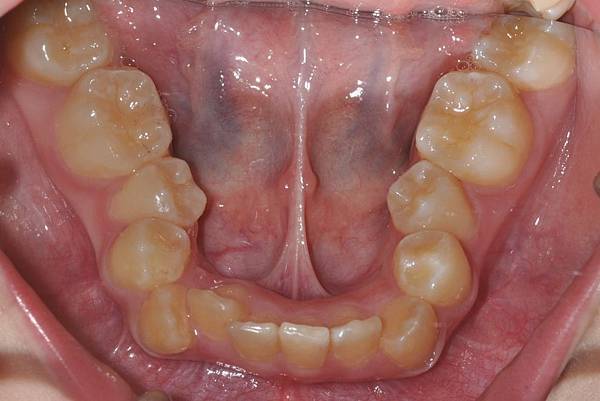

拔牙改善高位虎牙

虎牙妹的女神蛻變之旅~

此案例因為空間不足排列牙齒,

考量到不拔牙將使得牙齒前凸破壞患者原本和諧的側臉。

故上下左右各拔一小臼齒。